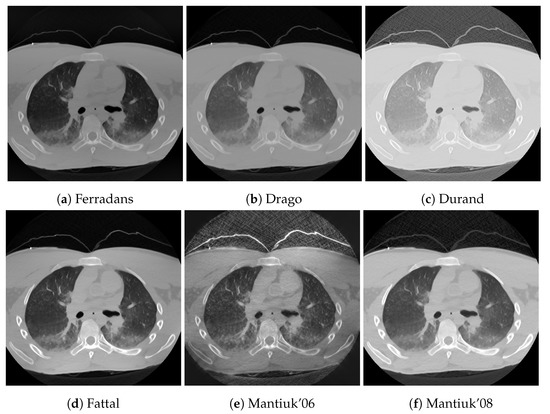

The results of our proposed algorithm are demonstrated in two ways. First, it has been compared to 8 different tone mapping operators, Ferradans [24], Drago [22], Durand [19], Fattal [21], Mantiuk ’06 [38] and ’08 [25], and Reinhard ’02 [20] and ’05 [23], using two post-mortem CT examples, a head and a chest CT. Second, the effects of changes of the algorithm parameters are depicted in two image montages, using the above-mentioned chest CT and a color photo of a ship, in Figure 4. The purpose of the ship image is to demonstrate that the algorithm is not specific to CT images. The image is an RGB image which was transformed to HSV color space [9], and the V component was processed using 256 discretization levels.

Next to the structural similarity, gradient magnitude and image entropy are also reported. These three quantitative results are presented in Table 2, while the tone mapped images are shown in Figure 5 and Figure 6.

The effect of the two control parameters, the exponent of the power-law, and the contrast limit is visualized in Figure 7 and Figure 8. Faster decreasing weights further enhance the local features, including noise. The contrast limit from CLAHE effectively regulates this issue.

Figure 7.

The effect of the weighting function and clipping. Rows from top to bottom have a = 0.7, 1.0, 1.5, 2.0, respectively, and the clip limits in the columns from left to right are 1, 5, 10 and 20, using units where N is the number of histogram bins.